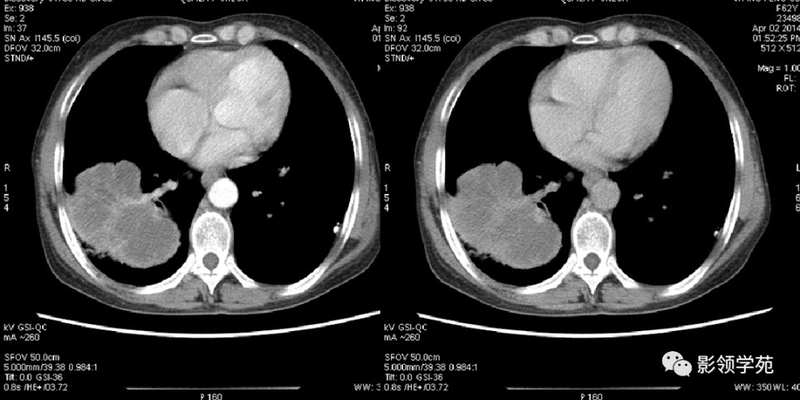

(1)较大含空洞性肿块,洞壁较厚,大于15mm,空洞外壁有分叶、毛刺,洞壁凹凸不平有壁结节,增强可见不规则强化,周围未见明显卫星病灶时,首先考虑周围型肺癌;癌性空洞洞壁一般肺门侧较厚,空洞多偏于外侧,伴有同侧淋巴结肿大更支持肺癌诊断。

(2)空洞病变发生于双肺上叶尖后段、下叶背段,病变周围可见点状、结节状及片状卫星病灶,洞壁组织无明显强化或有包膜线样强化时,考虑结核;结核球的空洞多位于病变的肺门侧,与引流支气管相同,洞内壁一般较光滑。